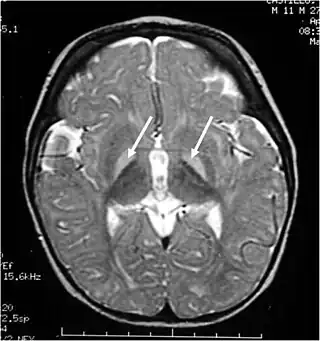

Resonancia magnética de la cabeza. Lesiones hiperintensas de los ganglios basales en T2, marcadas con una flecha blanca.